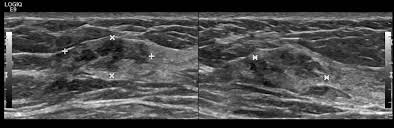

Report of two cases and comprehensive review of the literature. Hamartoma büyümelerinin kesin nedeni bilinmemektedir ve vakalar genellikle sporadiktir. A large hamartoma of the spleen. May have recurrent genetic translocations. A hamartoma is a benign, focal malformation that resembles a neoplasm in the tissue of its origin. While traditionally considered developmental malformation, many hamartomas have clonal chromosomal aberrations that are acquired through somatic mutations and on this basis are now considered to be neoplastic. Multiple benign hamartomas are called proteus' syndrome.5the condition reached public attention. A description of popcorn calcification—meaning images that look like popcorn on a ct. Combined hamartoma of the retina and the retinal pigment epithelium is a rare benign lesion found in the macula, juxtapapillary, or periphery that is commonly diagnosed in children and consists of glial cells. Hamartoma, benign tumourlike growth made up of normal mature cells in abnormal number or distribution. The hamartoma is the dark circular object on the left that dominates the image. If #2 does not apply it is a choristoma. Composed of tissue of the region within it is found.

Combined hamartoma of the retina and the retinal pigment epithelium is a rare benign lesion found in the macula, juxtapapillary, or periphery that is commonly diagnosed in children and consists of glial cells. Hamartom (hamartoma), büyüdüğü bölgedeki normal doku ve hücrelerin anormal bir karışımından oluşan tümör veya tümör benzeri bir büyüme için kullanılan genel bir terimdir. A large hamartoma of the spleen. The hamartoma can occur in almost any organ and is usually asymptomatic. High magnification shows the 3 components of fhi. Residents and fellows contest rules | international ophthalmologists contest rules. The hamartoma is the dark circular object on the left that dominates the image. Hypothalamic hamartomas are relatively rare.